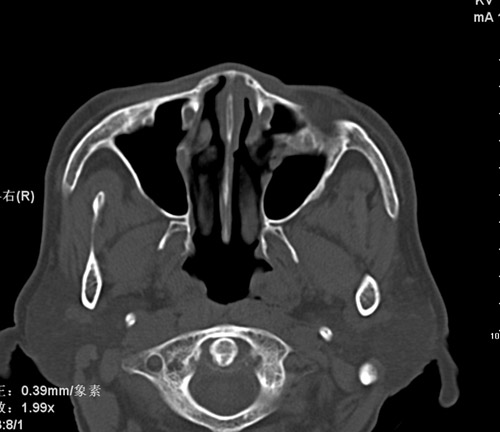

标题: CT17755:女,74 左鼻旁肿胀半年,临床以左上颌窦旁占位行CT [打印本页]

标题: CT17755:女,74 左鼻旁肿胀半年,临床以左上颌窦旁占位行CT

ct考虑鼻前庭囊肿 或鼻翼基底部慢性炎症,左上颌窦少许炎症 请指教

1)考虑左侧鼻前庭囊肿并感染。2)双侧上颌窦炎。

左侧鼻前庭囊肿并感染。双侧上颌窦炎。支持